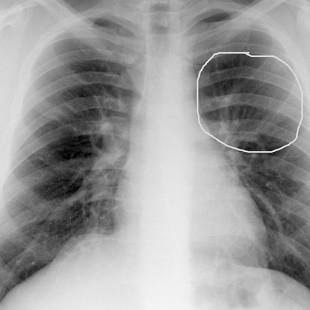

Segundo Pasqualete(1), membro do corpo clínico do CEPEM – Centro de Estudos e Pesquisa da Mulher, a notícia divulgada na Internet “quase todos os casos de câncer de mama acontecem no quadrante superior da área do peito, justamente onde os nó...